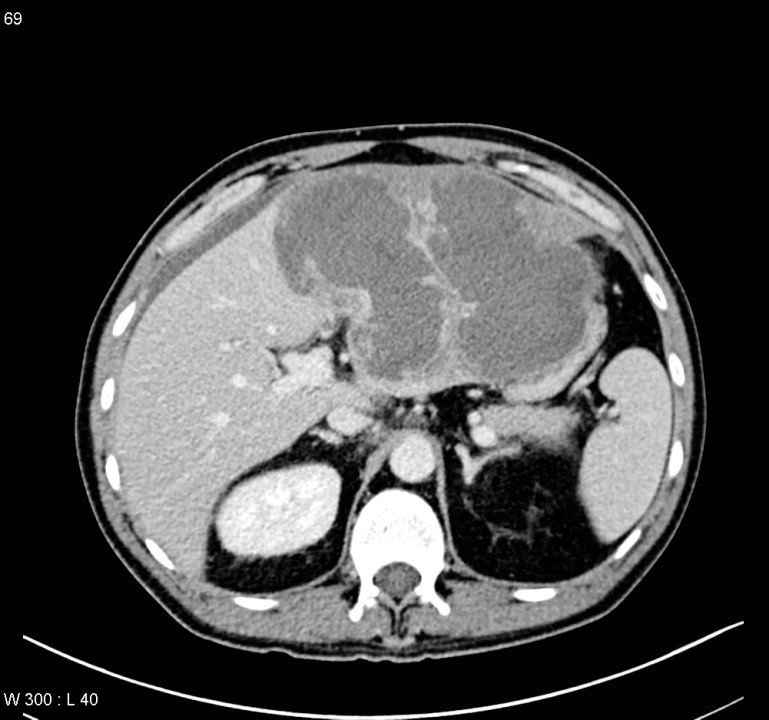

Abses diaqnozunu dəqiqləşdirmək üçün klinik əlmətlərlə yanaşı görüntüləmə və laborator müayinələr aparılmalıdır. Yerli və ümumi sepsis əlamətləri ilə yanaşı USM və ya tomoqrafiyada qaraciyərdə abses boşluğun görünməsi diaqnozu dəqiqləşdirir. Absesdə qaztörədən bakteriyalar olduqda və ya bağırsağa açılarsa içərisində qaz görünür (25%).

Diaqnostik əlamətləri:

• Ağrı, hepatomeqaliya, hərarət, septik əlamətləri

• Laborator septik əlamətlər

• Görüntüləmədə destruktiv ocaq